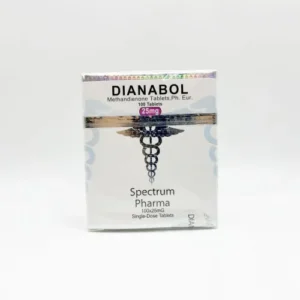

Branded vs. Generic Clenbuterol Formulations

Clenbuterol 40mcg is available under various brand and generic names worldwide, including Spiropent and Monores as branded formulations, and Astralean, Ventipulmin, and other generic-labeled variants depending on region and manufacturer. While branded formulations are typically standardized in quality, generics may vary in terms of excipients, bioavailability, and tolerability — especially when sourced from disparate regions. Most generic versions contain the same active compound (Clenbuterol hydrochloride), yet formulation differences can influence absorption, onset, and side effect profile.

For patients with sensitive digestion, known allergies, or previous reactivity to fillers, branded options may offer better consistency. However, reputable generics — when sourced from validated manufacturers — often perform equivalently in terms of efficacy and safety. Selection should be based on personal response, cost structure, and provider recommendations. In online settings, patients are advised to request known-label formulations or pharmacy-issued batch reports when possible.